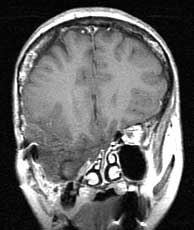

T1 coronals post gad

Findings:

Herniation of the right temporal lobe into the infratemporal fossa with no abnormal enhancement. A few scattered foci of increased signal unchanged compared to pre-gad coronals.